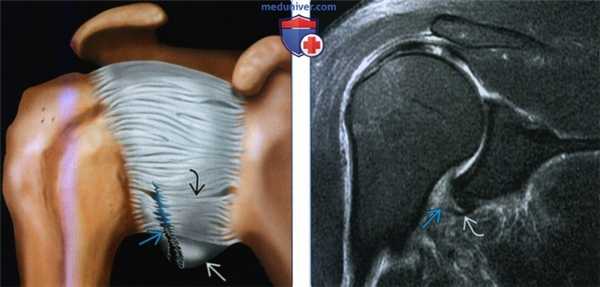

(Слева) На артрограмме Т1 FS с отведением и наружной ротацией у этого же пациента определяется повреждение в виде отрыва суставно-плечевой связки от плечевой кости, которое также захватывает переднюю часть нижней суставно-плечевой связки. Передний пучок нижней суставно-плечевой связки оторван от места прикрепления и наблюдается утечка контраста. При отрыве суставно-плечевой связки от плечевой кости с нестабильностью часто требуется оперативное вмешательство.

(Справа) На осевой MPT PDBИ FS можно видеть повреждение в виде свежего отрыва суставно-плечевой связки от плечевой кости с разрывом в переднем пучке нижней суставной-плечевой связки в месте прикрепления. Медиальная часть переднего пучка нижней суставно-плечевой связки извилистая, имеется отек и кровотечение в перикапсулярных мягких тканях.

(Слева) Разорванная нижняя суставно-плечевая связка захватывает как передний пучок, так и подмышечный карман нижней суставно-плечевой связки. Разрывы, захватывающие передний пучок нижней суставно-плечевой связки часто вызывают нестабильность, а в случае крупных разрывов может потребоваться хирургическая пластика.

(Справа) На фронтальной косой МРТ Т2ВИ пациента со свежим передним/нижним вывихом определяется разрыв нижней суставно-плечевой связки с окружающим отеком. Часть подмышечного кармана нижней суставно-плечевой связки может разорваться после как переднего, так и нижнего (luxation erecti) вывиха. Также видна часть интактной нижней суставно-плечевой связки.